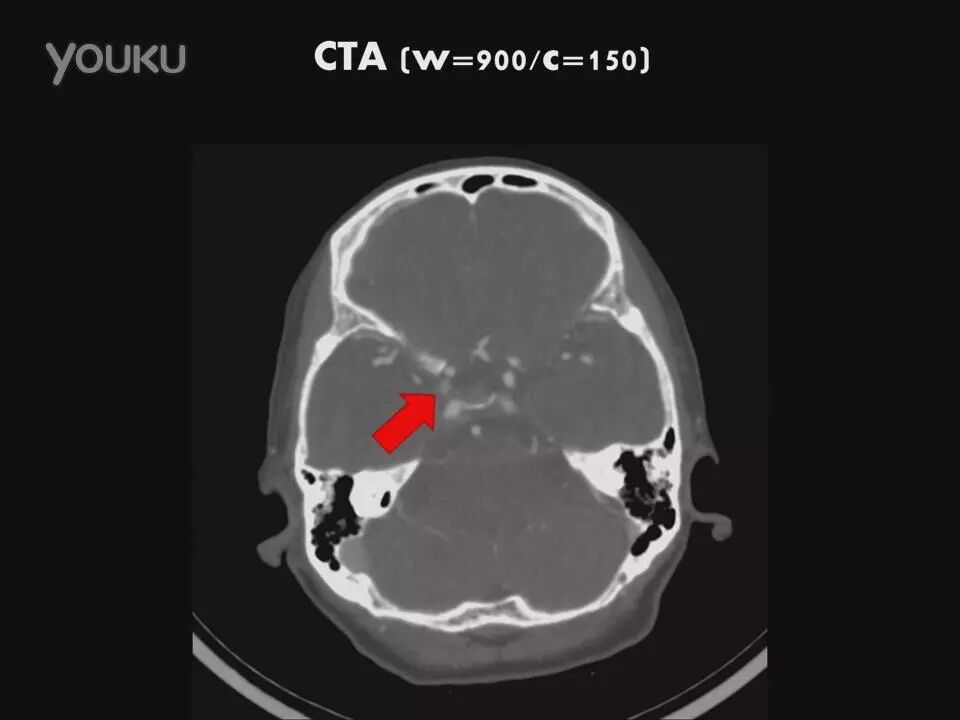

许秉权教授:显微手术钳夹海绵窦内动脉瘤